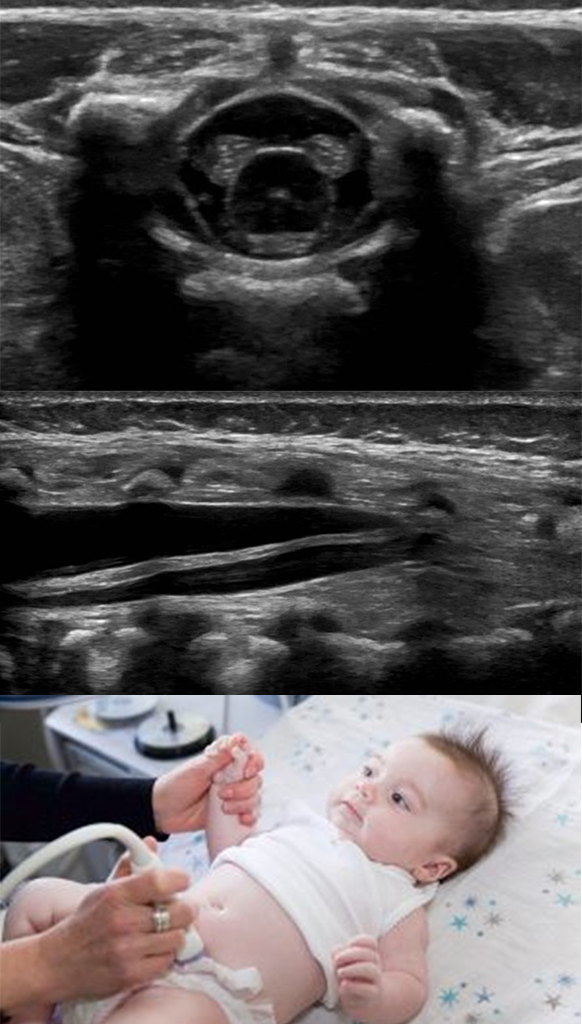

신생아 초음파

Neonatal Ultrasound

신촌 세브란스 교수 출신 임현지 원장님의 1만건 이상 소아초음파 경험으로 미숙아, 신생아 검진부터 희귀질환 초음파까지 모두 진료합니다.

갓난 아이들에게도 안전한 초음파 검사로, 건강상태를 꼼꼼하게 확인하세요.

초음파는 사람 귀에 들리지 않는 높은 주파수의 소리를 통해 이미지를 만드는 검사로, 방사선 노출이 없고, 인체에 해가 없으며, 재우거나 마취할 필요가 없는 안전하고 편한 검사입니다.

검사 시간도 5분 이내로 매우 짧아, 아이에게 무리가 없습니다.

딤플 초음파 엉덩이에 파인 것이 있는 경우 (3개월 이전 추천)

뇌 초음파 미숙아이거나, 머리가 유난히 큰 경우 (1세 이전 가능)

고관절 초음파 역아로 오래 있거나, 쌍둥이인 경우 (생후 4-6주 추천)

사경 초음파

상복부 초음파 간, 담낭, 담관, 췌장, 비장

콩팥과 방광 초음파 선천수신증

자궁, 난소, 고환 초음파

장 초음파 유문협착증(지속적으로 구토하는 경우), 장염, 장중첩증 등